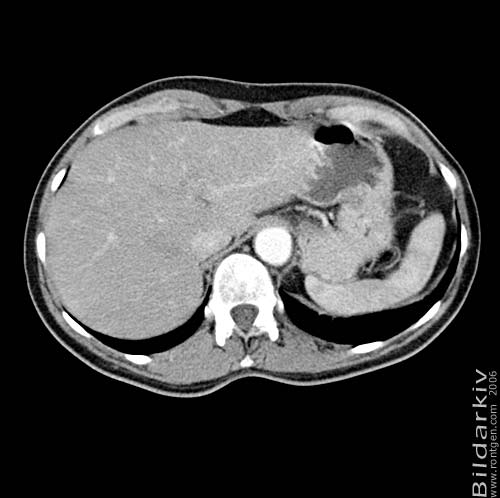

Thorax 53

Snitt över thorax med kontrast. Sk. mediastinum-fönstersättning.

CT Röntgen Helsingborgs lasarett

Mediastinum